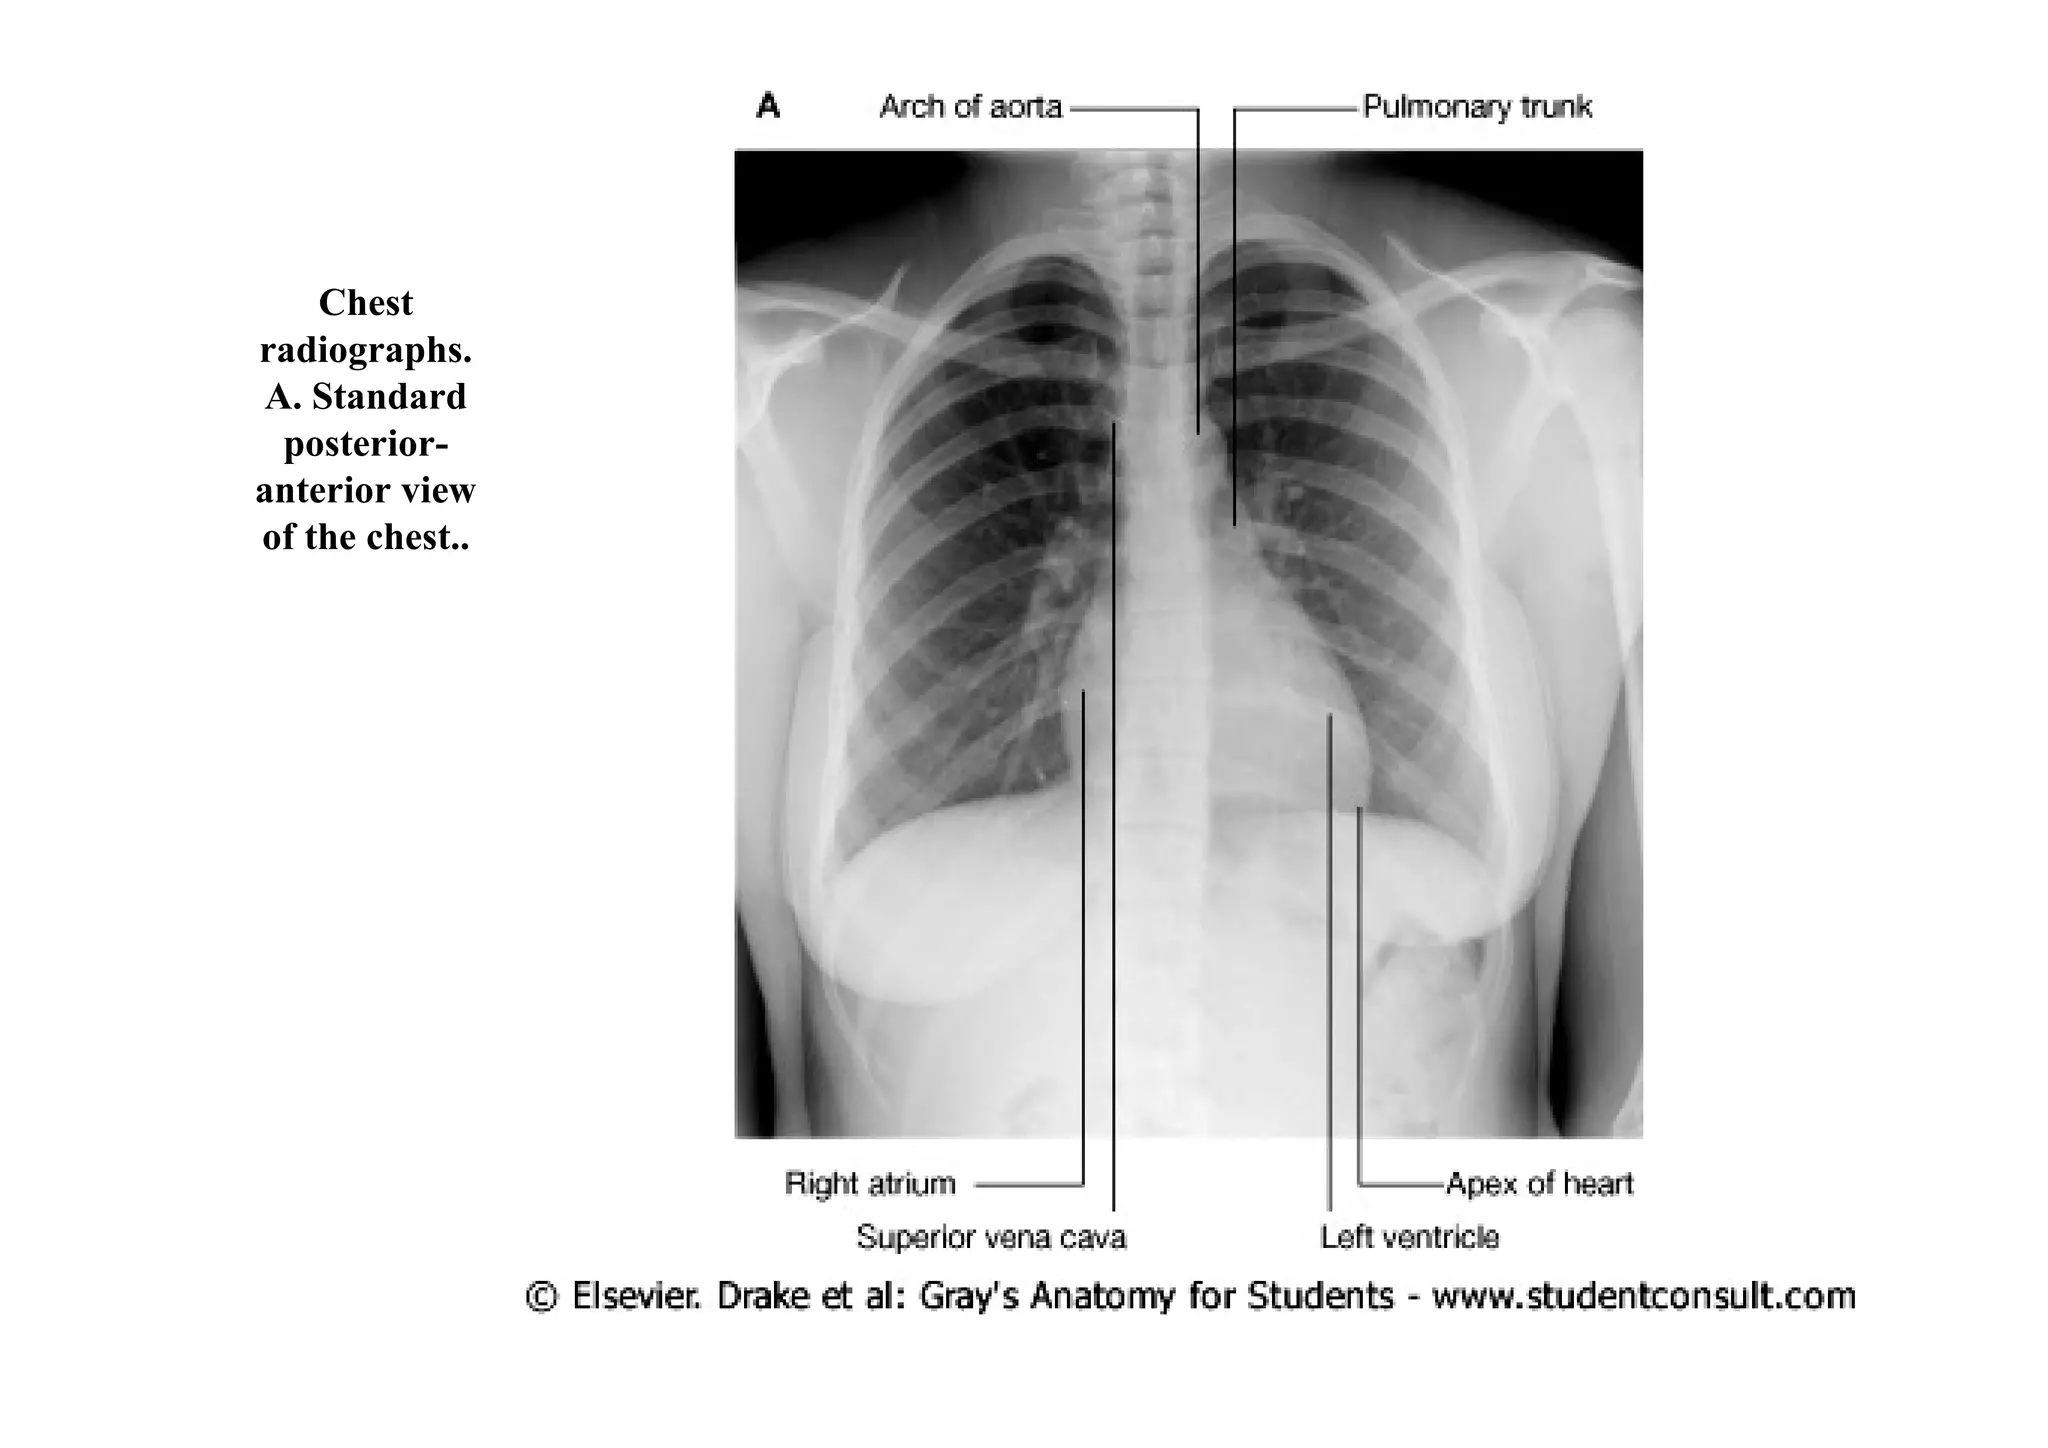

In lateral views, the right ventricle is seen anteriorly, and the left atrium is visualized

posteriorly

Chest radiographs.. B. Standard lateral view of the heart.